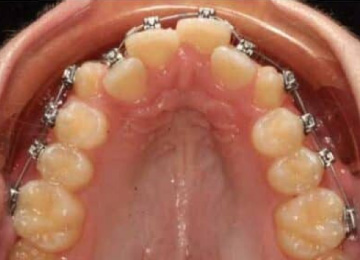

Одним из эффективных методов исправления прикуса у подростков после прорезывания зубов являются брекет-системы. Одним из препятствий к лечению во многих случаях становятся переживания подростков по поводу своего внешнего вида. В стоматологии "Интердентос" мы используем различные виды брекет-систем, в том числе и лингвальные, которые крепятся с внутренней стороны зубов.

Установка брекетов подросткам: фото До и После

- На 2-ом этапе происходит выбор наиболее эффективной и устраивающий подростка брекет-системы и установка.